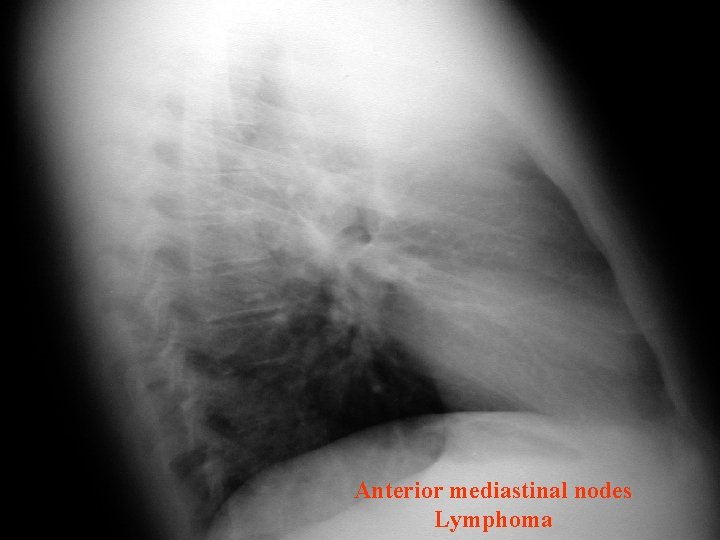

Anterior mediastinal nodes Lymphoma

Mediastinal Lesions • Anterior lesions – thymoma, thyroid lesions, teratoma, tcell lymphomas, and lymphadenopathy. • Usually seen in retrosternal space. anterior lesion. Lymphoma

Mediastinal Lesions • Lateral view shows a solid tissue density in the region anterior and superior to the heart. • Lymphoma is the most common anterior mediastinal mass. Lymphoma

Mediastinal Lymphoma • Mediastinum is involved in 50% Hodgkin’s diseases • Most cases are of nodular sclerosing type • Treatable and many are curable too • Intensive chemotherapy or radiotherapy or both • Radio alone relapse 50 -74% • Chemo alone relapse 33 -50% • “MOPP” or “DBVD” followed by radio preferred